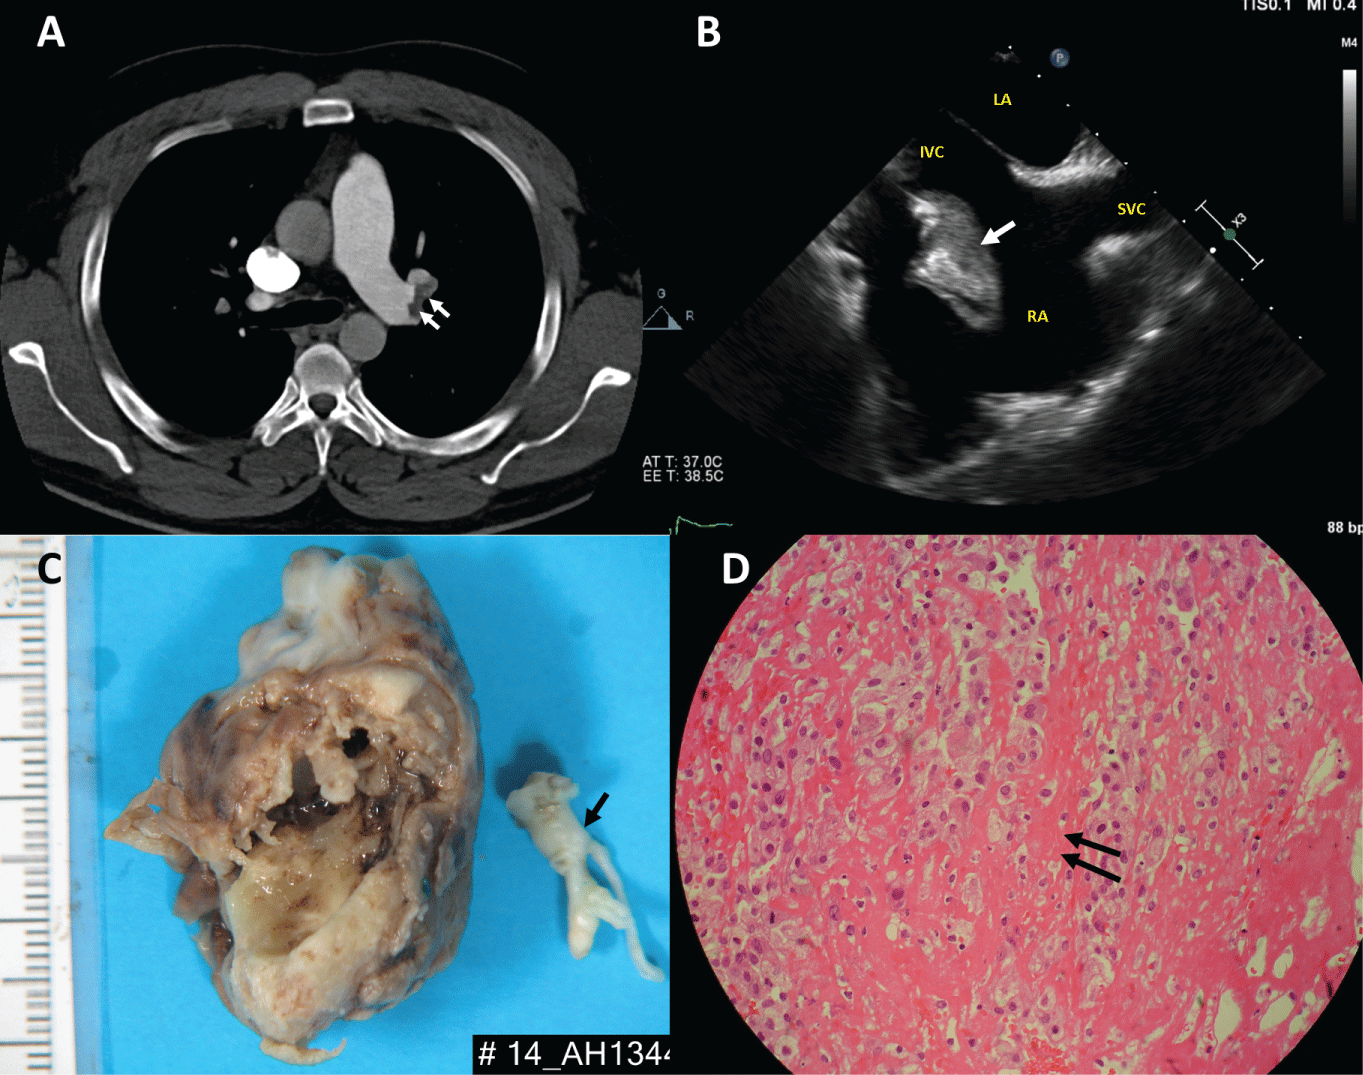

30-year-old man normally fit and healthy presented with collapse and palpitation. He was tachycardic with a heart rate of 120 beats/min and hypoxic with oxygen saturation of 85% on arrival. CT pulmonary angiography confirmed extensive bilateral segmental and sub segmental pulmonary emboli with evidence of right heart strain (Panel A). Laboratory data revealed an elevated international normalized ratio (INR) of 1.4, prolonged partial thrombo plastin time (aPTT) of 49 seconds and a low fibrinogen level of 1.0g/L. Blood cultures were unremarkable. CT abdomen and pelvis showed no evidence of malignancy.

Heparin was administered in view of his coagulopathy. Again, his coagulopathy resolved the following day. Trans oesophageal echocardiography confirmed a large right atrial mass measuring 3.9cm x 1.8cm with a stalk attached near the inferior vena cava (IVC) (Panel B, Online video). There was no obstruction to the tricuspid valve. An urgent operation was performed in view of the risk of further pulmonary embolism. On opening the right atrium a large tumour was found (Panel C) It was attached by a stalk to the eustachian valve and was very close to the IVC cannula. There were no other clots or tumour seen in the right atrium or ventricle. The tricuspid valve appeared normal. No myxo matous tumour was identified on H&E stained sections but only abundant partially organised blood clot with degenerate stroma (Panel D). The patient had an uncomplicated recovery and was discharged home on warfarin 6 days after the surgery. Post-surgery echocardiography confirmed no residual mass in the right atrium and he had no further coagulopathy.